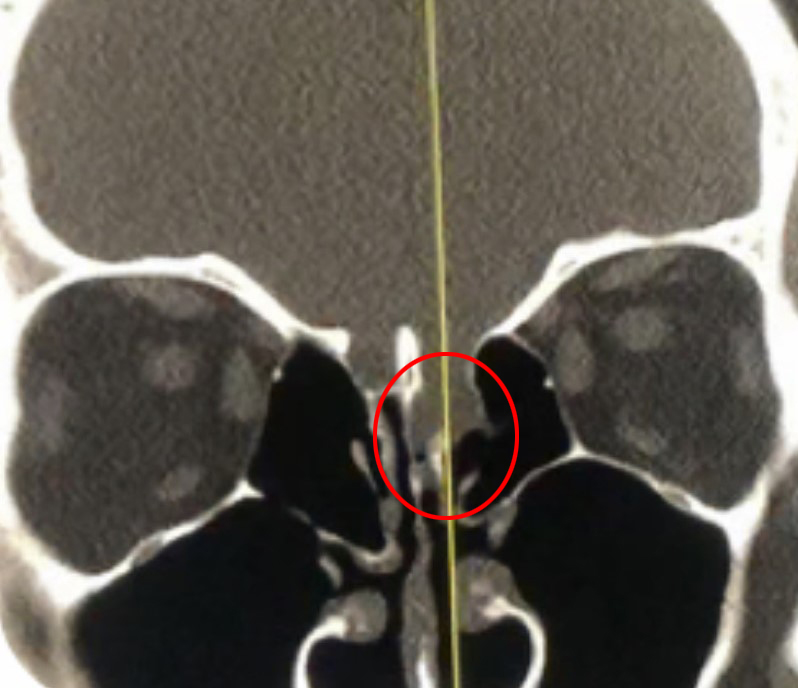

This is a 39 year old physician with a long history of sinus issues, who more recently had noted an increased drainage of clear fluid from his nose. Testing of the fluid for Beta-2-transferrin demonstrated that it was consistent with cerebrospinal fluid (csf). MRI and CT scan demonstrated an encephalocele in the frontal most part of the anterior skull base, on the left, just off midline (Figures 1a,1b,1c). For the last 3 weeks, he has also been having headaches and neck pain.

Figure 1b – Sagittal CT bone window